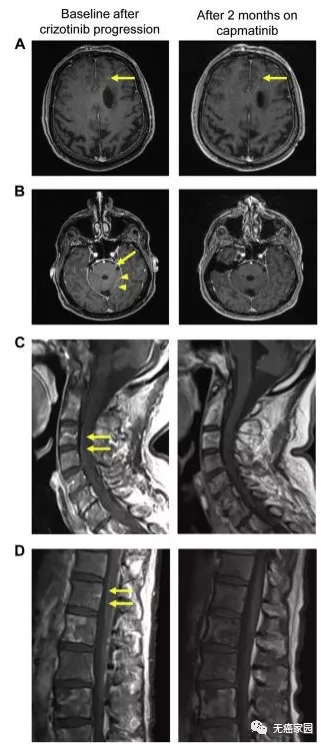

02、克唑替尼治疗复发后,卡马替尼高效抗脑转,力挽狂澜

这是一名75岁的不吸烟男性患者,被诊断为转移性肺腺癌,携带MET 14外显子突变,无其他靶向致癌突变。在初诊时患者的左肺、胸膜、淋巴结、骨和软组织存在广泛转移。在使用克唑替尼治疗9个月后,胸部、腹部和盆骨疾病部位出现明显反应,达到显著缓解。

图为患者初诊(左)及克唑替尼治疗9个月后(右)对比图

但不巧的是,病情急转直下,在治疗9个月后,患者开始出现脱水、低钙血症及精神错乱等问题,甚至还发生了脑实质和转脑膜转移,一直延伸到脊髓。在这万般危急时刻,医生经患者同意后,给其试用了卡马替尼,患者的病情迅速得到改善。

服用2个月的卡马替尼后,患者脑部左额叶的5 mm病变变成残留的的点状病变,病灶几乎快消失;左三叉神经和左小脑半球叶的软脑膜病变已检测不到病灶;治疗后软脑膜沿脊髓的增强信号也彻底消失。